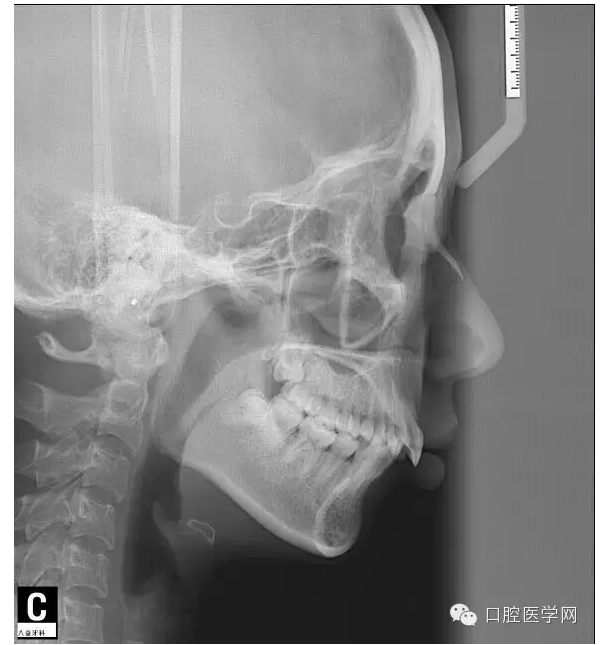

這是一位我同事接診的一位患者,成年女性,安氏II類,高角,下頜后縮,重度深覆合,上下中線右偏,原本做過一次矯正,4個4已經(jīng)拔除。

這個患者,II類高角,下頜后縮,所以我們不能抬高磨牙,另外兩個上頜中切牙牙根短小,也不能大幅壓入。

所以這個患者我選擇使用弓絲壓低下前牙。但由于雙尖牙只剩下15,45,所以我們將37,47,納入矯正。